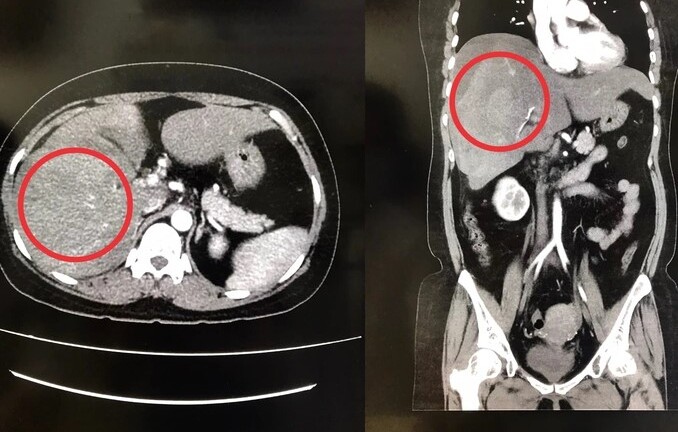

Bệnh nhân được chẩn đoán ban đầu là chấn thương sọ não; chảy máu dưới màng cứng; chấn thương ngực nghi tổn thương nhĩ phải gây chèn ép tim, chấn thương bụng nghi vỡ gan chảy máu ổ bụng; chấn thương vỡ tạng rỗng, chấn thương gãy 2 xương cẳng chân phải.

Ekip phẫu thuật Tim mạch được ưu tiên phẫu thuật xử trí tổn thương nhĩ phải để giải phóng chèn ép tim. Sau đó, các bác sĩ phẫu thuật tiêu hóa mở ổ bụng, xử trí tổn thương gan trái vỡ đứt rời, gan phải vỡ phức tạp hạ phân thùy 6-7-8 kèm theo đụng dập chảy máu mạc treo ruột non và vỡ ruột non nhiều vị trí. Các bác sĩ đã tiến hành cắt gan trái, cầm máu gan phải, cắt bỏ đoạn ruột dập vỡ đưa 2 đầu ruột ra làm hậu môn nhân tạo.